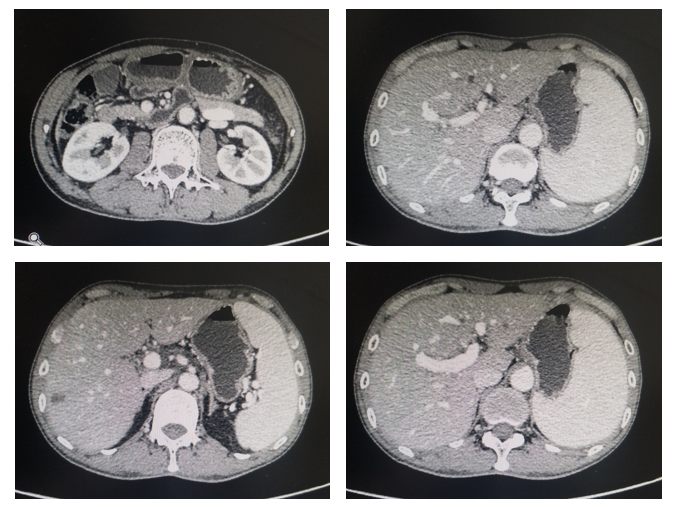

评估:治疗后3月和5月复查腹部CT情况(图2和图3).

图3. 腹部CT平扫+强化(治疗后2月,2020年1月)

图4. 腹部CT平扫+强化(治疗后5月,2020年3月)

影像科:根据患者治疗前、治疗后首次及再次复查CT看,原发病灶胃壁增厚明显减轻,肝转移病灶明显缩小,部分病灶消失,首次CT判效PR,再次复查CT确认PR。提示内科治疗有效。